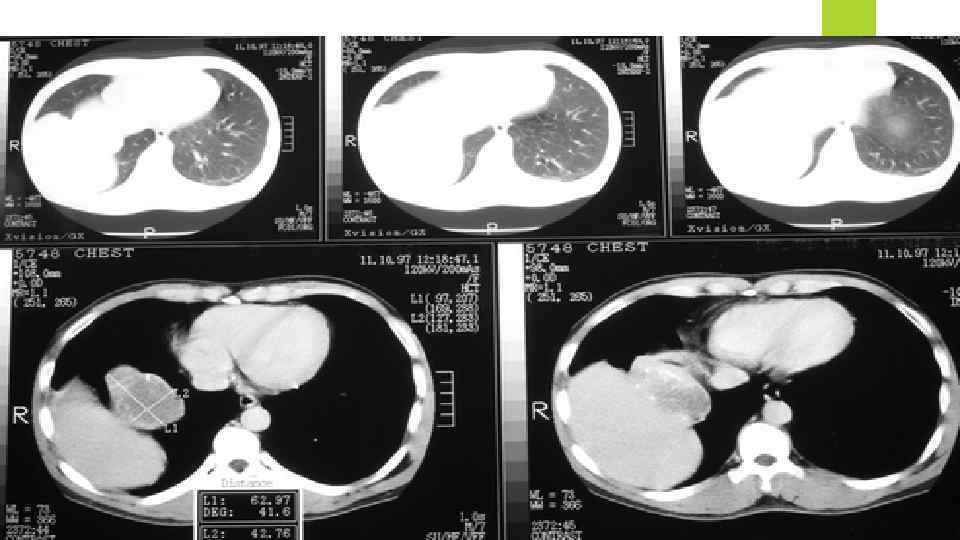

Компьютерная томография: При помощи компьютерного томографа делают снимки не только грудной клетки, но и живота и мозга. Все это делается с целью определить - нет ли метастаз в других органах. Компьютерный томограф более чувствителен к узелкам в легких. Иногда, для более точного обнаружения проблемных мест, в кровь больного вводят контрастные вещества. Само компьютерное сканирования обычно проходит без всяких побочных эффектов, но ввод контрастных веществ иногда вызывает зуд, сыпь и крапивницу. Также как и рентгенография грудной клетка компьютерная томография только находит проблемы места, но не позволяет точно сказать рак это или чтото другое. Для подтверждения ракового диагноза требуются дополнительные исследования.

Компьютерная томография: При помощи компьютерного томографа делают снимки не только грудной клетки, но и живота и мозга. Все это делается с целью определить - нет ли метастаз в других органах. Компьютерный томограф более чувствителен к узелкам в легких. Иногда, для более точного обнаружения проблемных мест, в кровь больного вводят контрастные вещества. Само компьютерное сканирования обычно проходит без всяких побочных эффектов, но ввод контрастных веществ иногда вызывает зуд, сыпь и крапивницу. Также как и рентгенография грудной клетка компьютерная томография только находит проблемы места, но не позволяет точно сказать рак это или чтото другое. Для подтверждения ракового диагноза требуются дополнительные исследования.